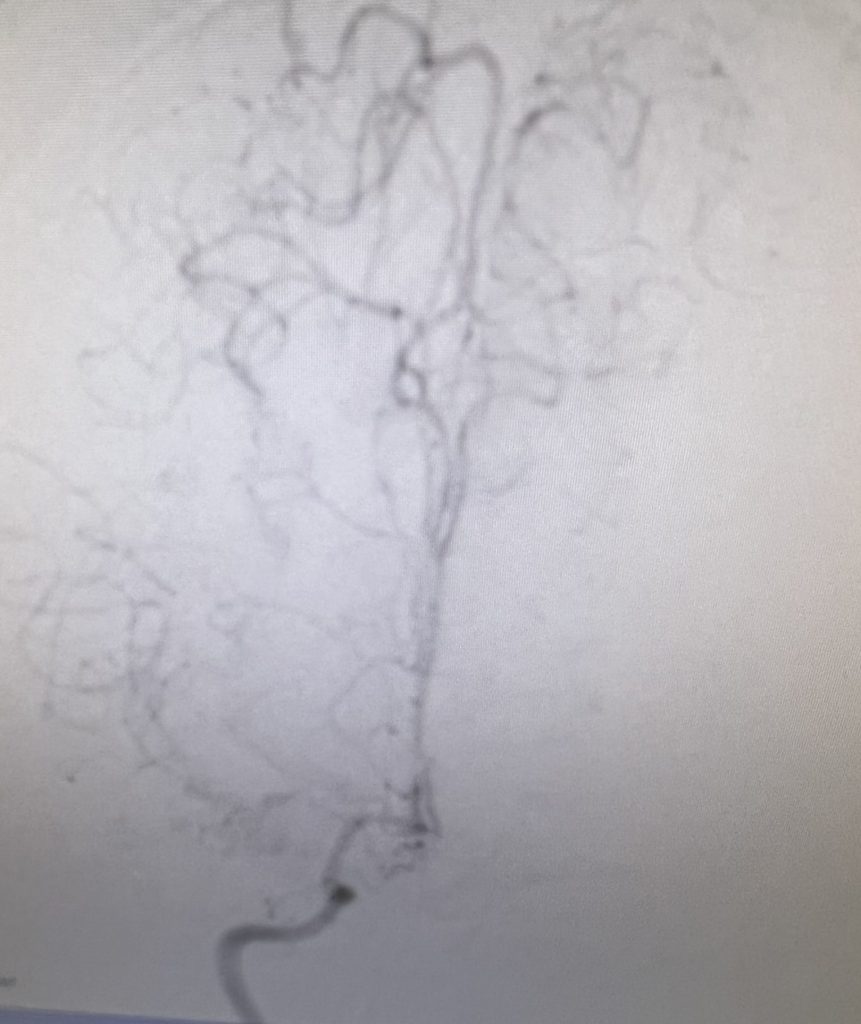

Figure 2

Noninvasive vascular imaging was sufficiently suggestive to warrant conventional digital subtraction angiography, performed by Dr. Brisman and confirming Moya-Moya syndrome (Figures 1). CT Perfusion (Figure 2) showed a decreased transit time of blood to the right hemisphere and the patient was recommended to undergo cerebral revascularization to avert stroke.